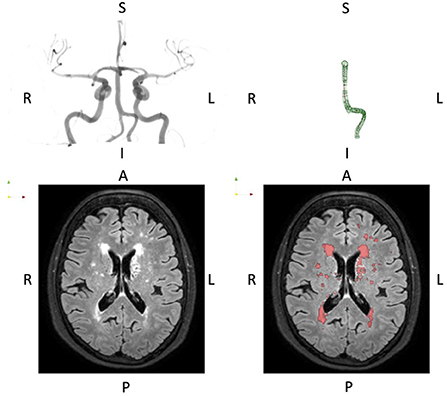

Figure 1 shows raw imaging data and associated processing for a typical subject.

Figure 1

Typical presentation of basilar artery geometry (top row) and WMH burden (bottom row). The basilar artery segmentation is the full P1-P4 segment thus including the dominant vertebral artery segment. The orientation is indicated by the letters A, Anterior; P, Posterior; L, Left; R, Right; I, Inferior; S, Superior.